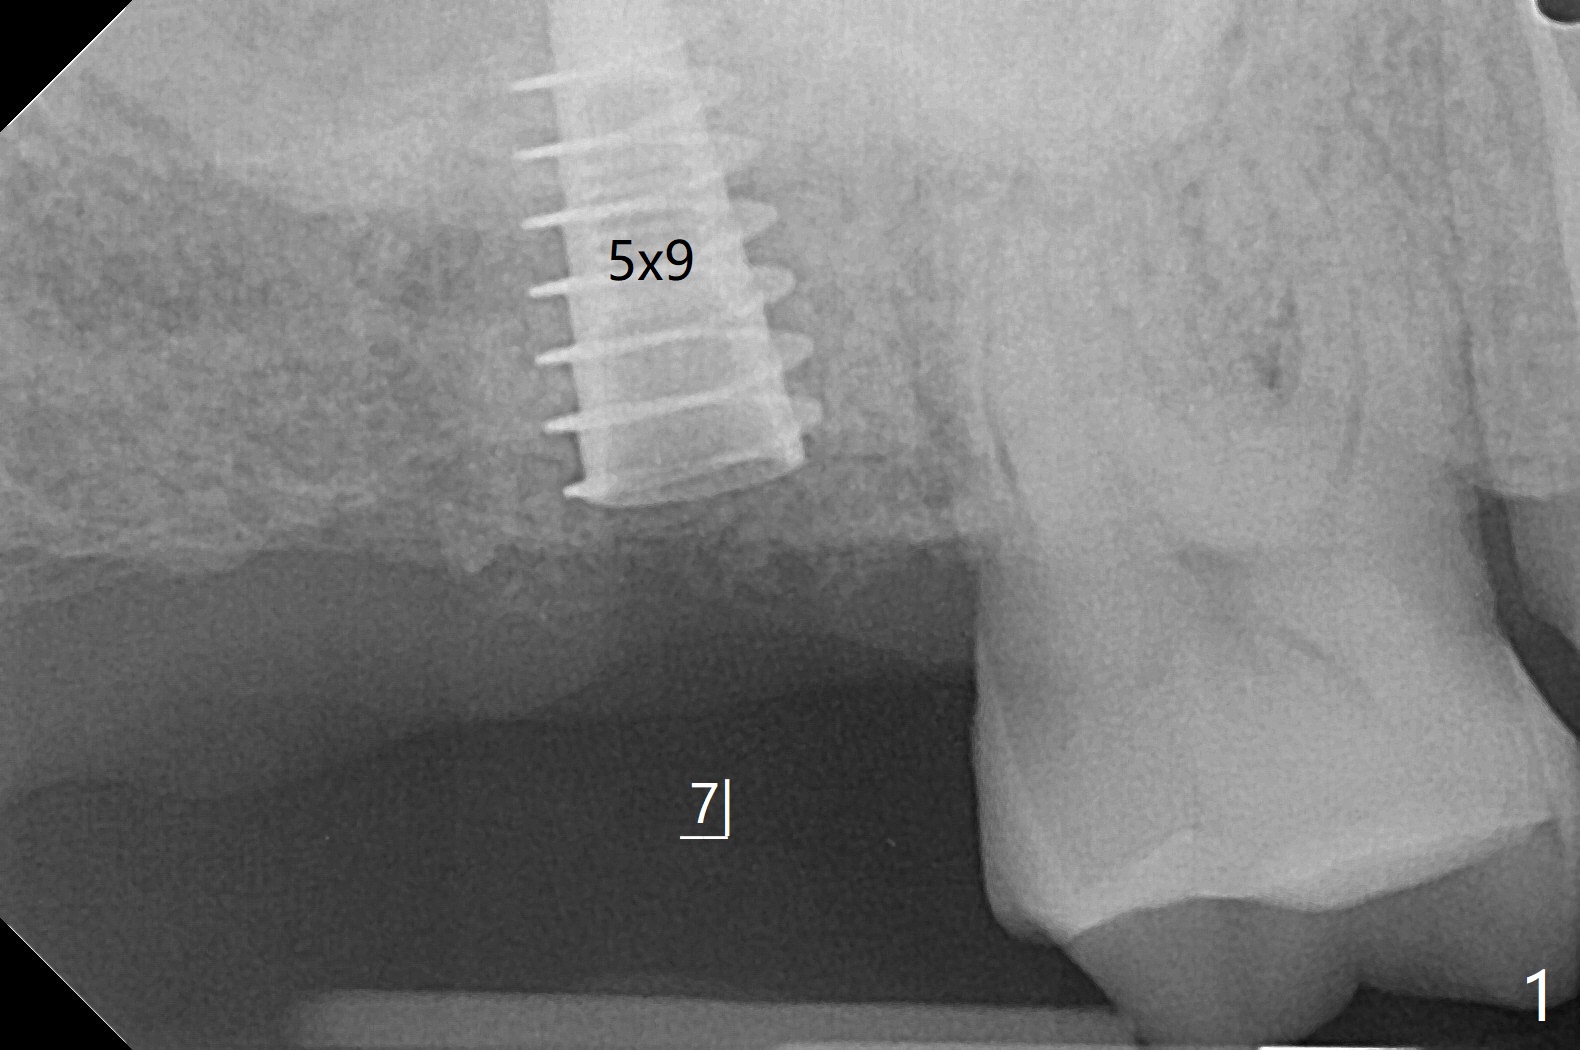

66岁男右上,左上7导板延期种植(足够角化龈,使用环形切刀),都提升,但是前者未植骨(图一,二(骨高度多,进入上颌窦少)),后者植骨(图六(*),七),由于扭力低(小于15Ncm),放置愈合螺帽和剪成圆形六个月胶原膜,使用牙周胶水(图三,八),之后不再放置牙周敷料。当钻头接近左侧上颌窦底板时,放置骨粉(图四-六:*),使用报废植体(图四,五)和正式植体(图六)将骨粉推入上颌窦。术后病人抱怨食物撞击伤口疼痛,即刻修复减少术后疼痛。术后5个月没有骨质吸收,基台完全就位(图十一,二)。